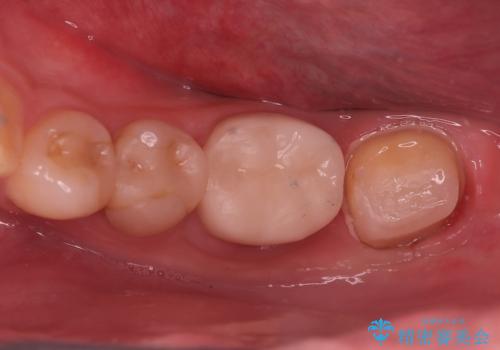

レントゲンや口腔内所見にて以下のような説明ののち、患者様が保存を希望されたため、当院では根管治療~オールセラミッククラウンにて修復処置を行いました。痛みも消えて、経過良好です。

治療選択肢として、①何もしない、②根管治療、③抜歯を説明した。

根尖部に透過像を認め、①何もしないと今後の経過として痛みが増悪することや、腫脹を伴うことがある。

病気の原因は細菌であるため、細菌数を減らすための処置として一般的に②根管治療という選択肢がある。再根管治療の場合は病気が治るのは7割ぐらいであり、それでも治らない場合は意図的再植術を行い9割近くまで成功率を高めることができる。ただし、今回のケースでは根尖が湾曲しているため意図的再植時の破折リスクが高いため適応は難しい。また、根尖の病変が治ったとしても、歯周病、カリエス、脱離や破折リスクがあり治療後抜歯になる可能性もある。治らない可能性や治療したとしても抜歯になる可能性があることを考慮し、③抜歯の選択肢をとる場合もある。